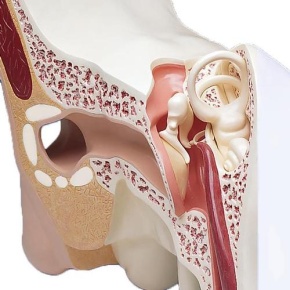

Nase und Riechorgan, 4-fache Größe

Modell, Nase und Riechorgan, 4-fache Größe